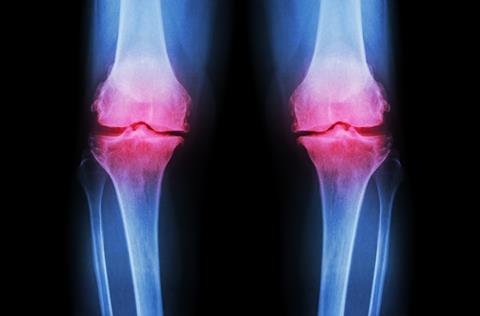

OA, a debilitating joint disease which affects over 500 million people worldwide, is caused by progressive, irreversible degeneration of joint cartilage. This results in pain, swelling and immobility, which can be relieved by current therapies, but they cannot restore degenerated cartilage.

In the new study, the researchers investigated limb bud progenitor cells. These cells, during vertebrate embryogenesis, differentiate into limb cartilage, bone, and tendon, suggesting that this type of stem cell has a naturally high intrinsic capacity to make cartilage. The researchers used genetic tools to isolate limb bud progenitors from developing mouse embryos. Notably, when injected into knee joints of mice with OA, the limb bud progenitor cells efficiently generated new cartilage. MSCs given to a separate group of mice failed to do so.